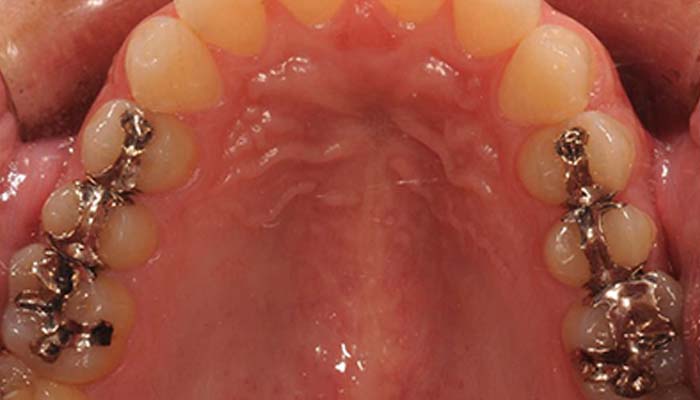

臼歯部セラミックインレー症例

治療前

治療後

保険の金属ではどうしても年数がたってくると、歯と金属の間にすき間ができてきます。 そのすき間から細菌が入り、中で虫歯になってしまう可能性が高くなります。それをセラミックインレーやコンポジットレジンを用いることで歯と接着してくれるため、歯を削る量を減らせたり、虫歯になる可能性を低くしてくれます。